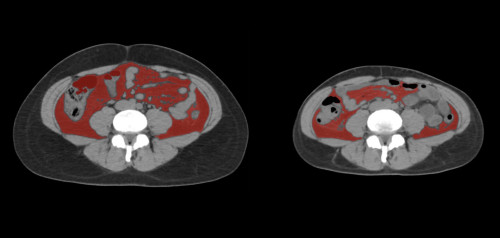

①

50代・女性(ご本人のご厚意で画像提供)

治療内容:チルゼパチド7.5mgの週1回自己注射による脂肪減少と脂肪肝改善

治療期間: 12ヶ月(52週)((用量は2.5mgから開始し最大で15mg。減量効果が得られる必要用量には個人差があります。))

費用:自由診療の場合は9900円(税込)×52(週)=514800円

想定されるリスク・副作用:下記に副作用を記載

※医療広告ガイドラインに準拠して表記

1:脂肪の減少

皮下脂肪の減少(赤色部分)